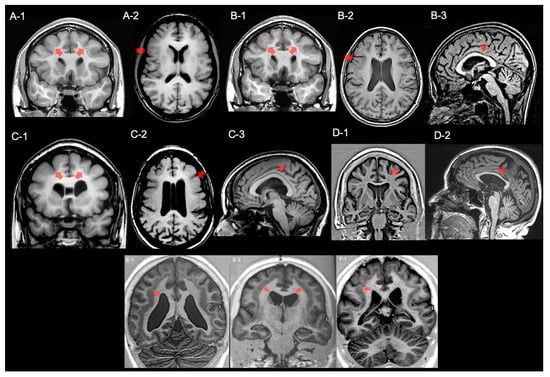

2.1. Electroclinical and Neuroimaging Data

2.1.1. Family 1

2.1.2. Family 2

2.1.3. Family 3